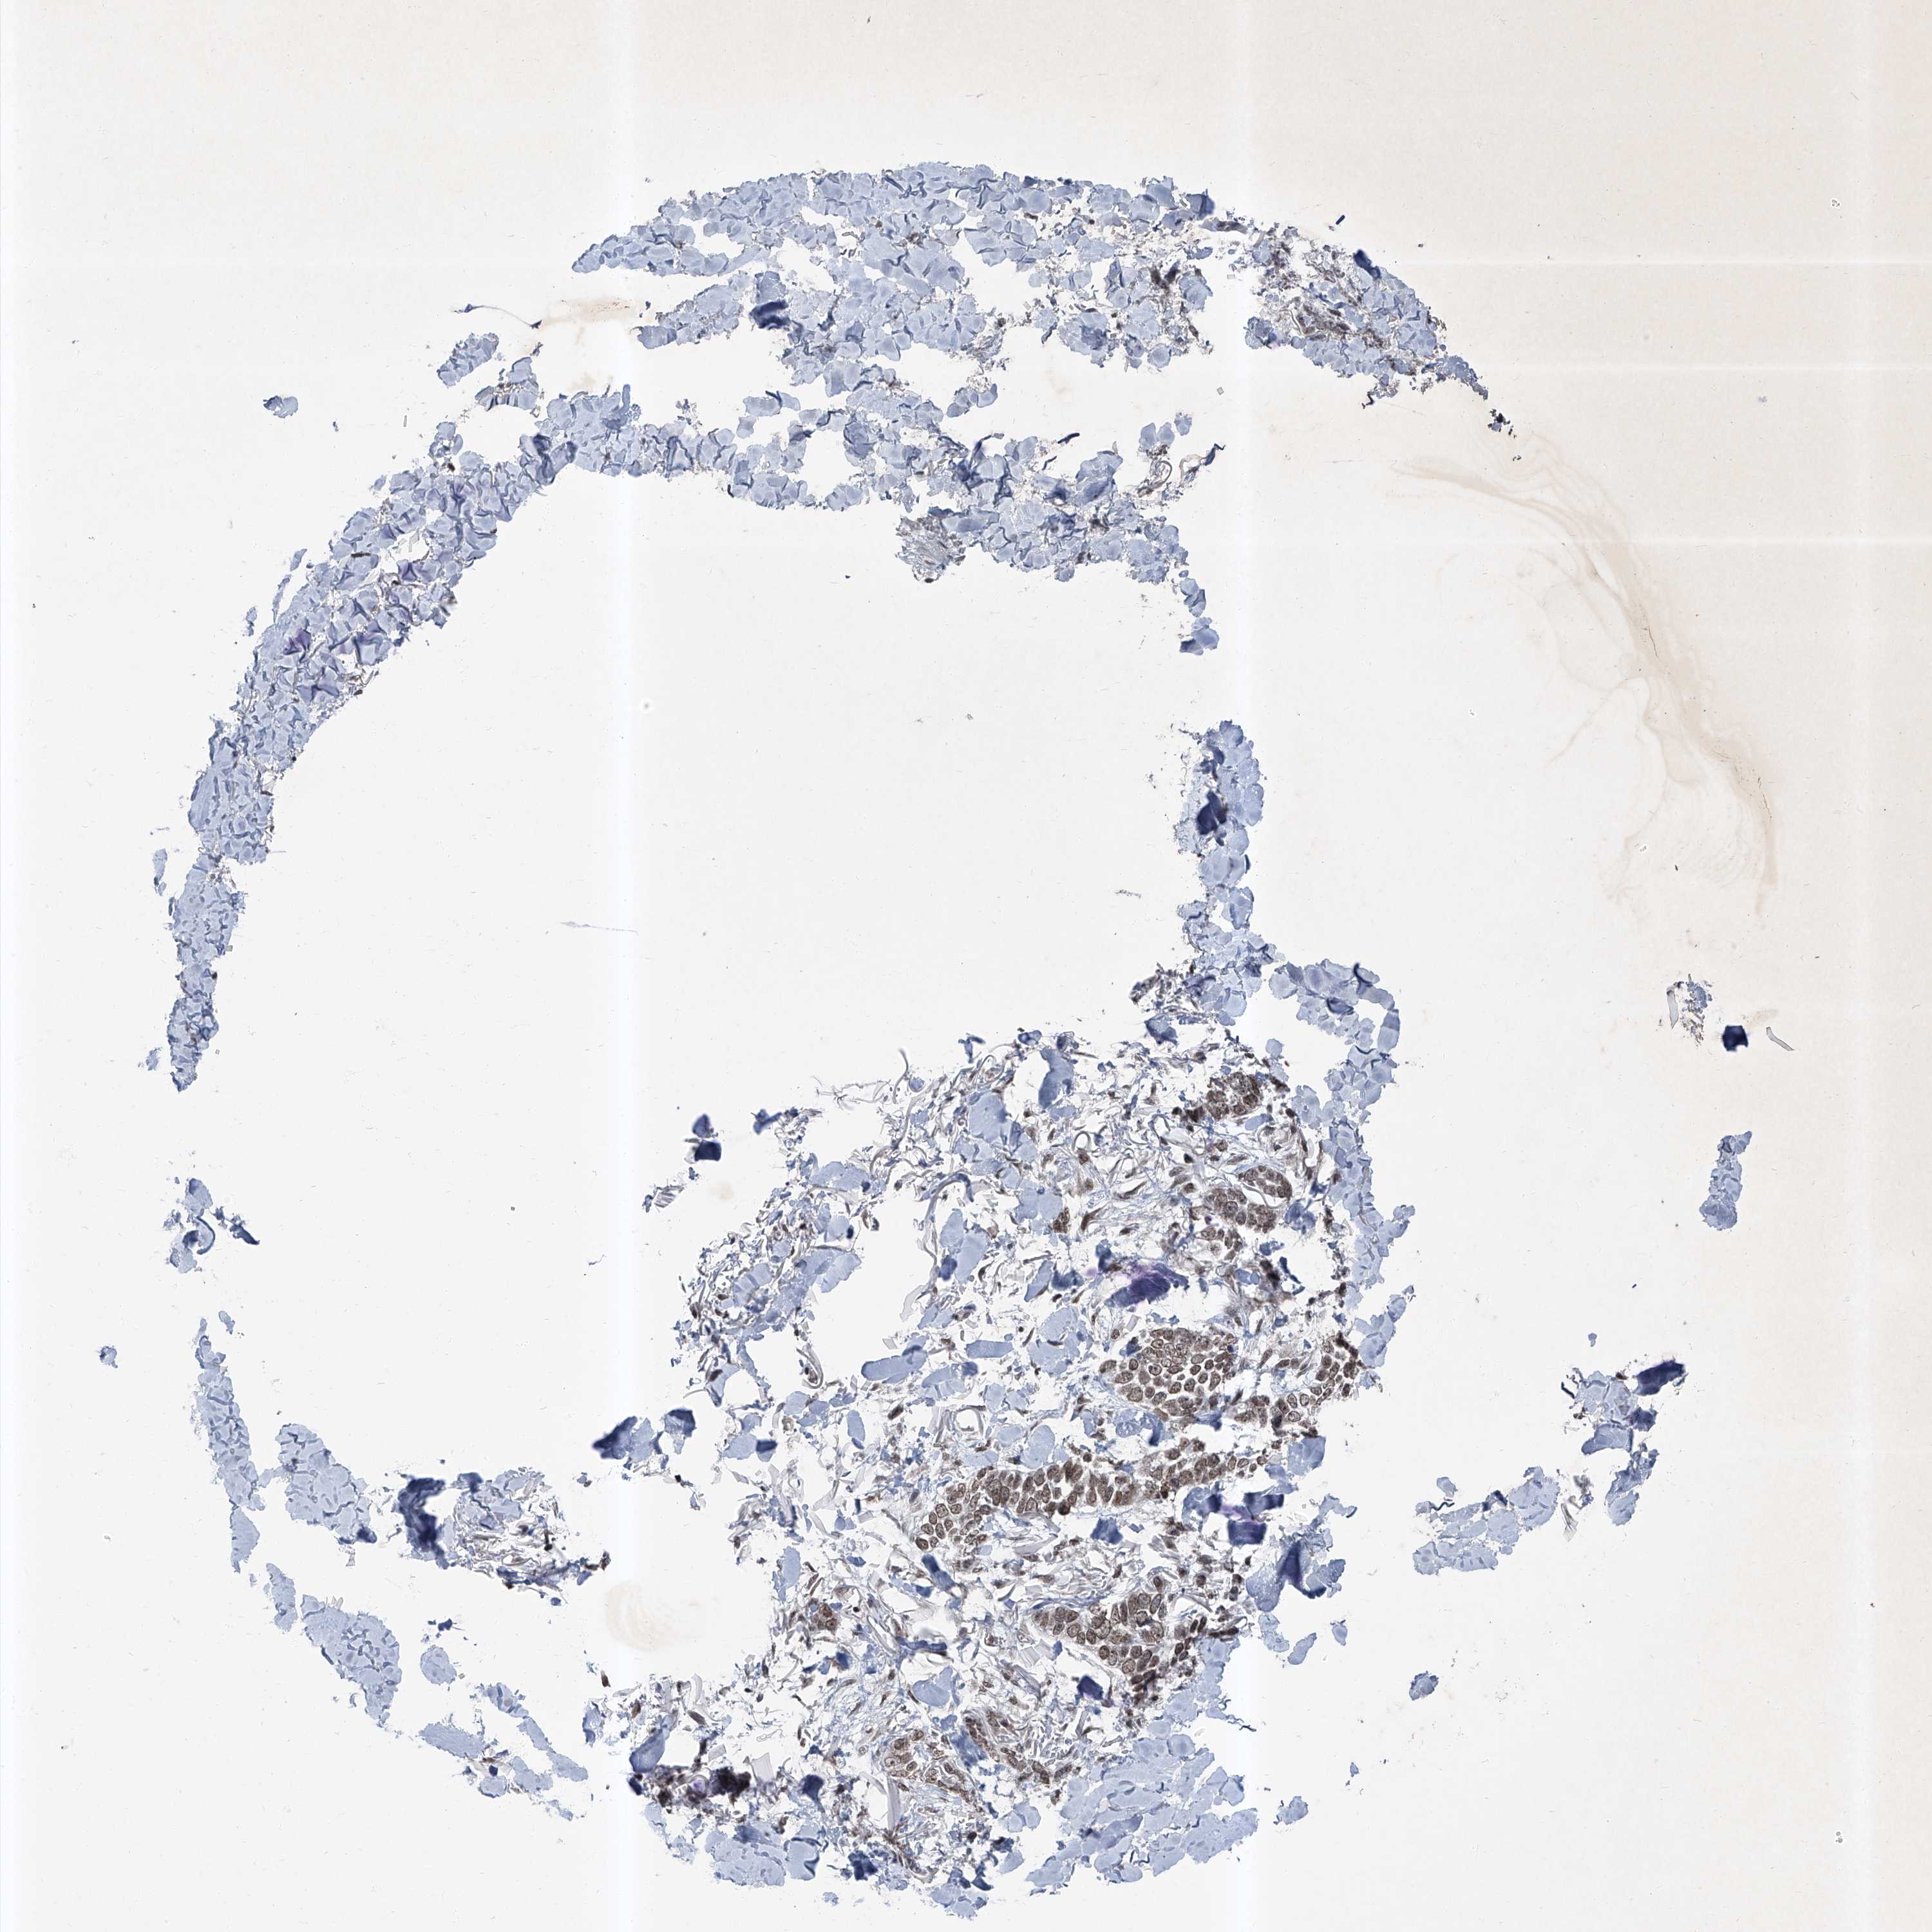

Basal cell and squamous cell cancer

SKIN CANCER - Protein expressioni

A mouse-over function shows sample information and annotation data. Click on an image to view it in a full screen mode. Samples can be filtered based on level of antibody staining by selecting one or several of the following categories: high, medium, low and not detected. The assay and annotation is described here.

Each image is clickable and will lead to virtual microscopy that enables deeper exploration of all samples and also displays staining intensity scores, fraction scores and subcellular localization as well as patient and tissue information for each sample.

Antibody HPA030472

Basal cell carcinoma

Squamous cell carcinoma, NOS

Squamous cell carcinoma, metastatic, NOS